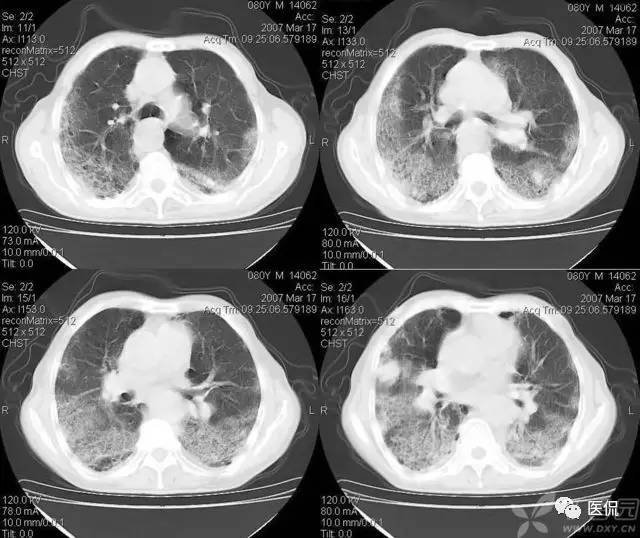

碎石路征

碎石路征或称铺路石征,是胸部CT上的一种影像学征象,主要表现为在弥漫性或散在分布的毛玻璃样浸润影中,有小叶间隔增厚、小叶内线状影重叠存在。碎石路征最初在肺泡蛋白沉积症(PAP)的病例中发现,并认为是PAP特征性的胸部CT表现;但实际上,感染性疾病、肿瘤、特发性肺弥漫性疾病(DPLD)、吸人性病变等都也可以出现。

1、感染:

1)卡氏肺囊虫肺炎(PCP):PCP是由卡氏肺抱子虫引起的肺部机会性感染,多发生于免疫功能严重受损者,是艾滋病(AIDS)患者发生机会性感染和致死的主要原因。PCP的主要症状包括干咳、呼吸困难和低热。典型的胸部X光片改变是双侧、沿肺门周围分布的网状影和境界不清的毛玻璃影;这种改变在CT上则表现为典型的碎石路征。引起碎石路征的病理学基础是:毛玻璃影由肺泡内泡沫样渗出,伴肺泡壁增厚引起;小叶间隔内水肿和慢性炎症细胞浸润致小叶间隔增厚、小叶内线状影。

2)严重急性呼吸综合征(SARS):SARS是一种起病急、病情发展迅速、人群普遍易感、死亡率较高的新的传染性肺部疾病。病理改变主要表现为弥漫性肺泡损伤(DAD),即肺充血、出血、水肿、透明膜形成、肺泡上皮细胞增生,部分肺泡腔内可见到脱屑的肺泡细胞、巨噬细胞和多核巨细胞,伴间质中炎症细胞浸润。主要临床表现是:发热(体温>38℃)、咳嗽、气短、呼吸困难等。胸部X光片可见大片状或斑片状分布实变影。部分SARS患者在起病2周内胸部CT上可发现碎石路征;在疾病的不同时期CT的表现形式有所不同,当早期以分散的、局灶性毛玻璃影为主要表现时,可见碎石路征,继而可以出现实变、间质增厚、胸膜反应和疤痕组织。

1)PAP是一种罕见病。各个年龄均可发病,以20~50岁的成年人多见。干咳、呼吸困难是其最常见的临床症状,而胸膜性胸痛、乏力、低热等则较少见。其胸部X光片表现是双侧对称性的肺泡实变或毛玻璃影,主要分布于肺门及肺门周围而类似肺水肿。CT的典型表现包括:①毛玻璃影及实变影与小叶间隔增厚交织形成碎石路征样改变;②在肺泡实变与正常的肺实质之间出现很明显的分界线,形成“地图样”分布。PAP碎石路征的组织学基础是:毛玻璃影及实变影与肺泡内充满PAS染色阳性、富含脂质的蛋白样物质有关;小叶间隔增厚影与肺泡壁因纤维组织增生或II型肺泡上皮细胞增生及淋巴细胞浸润有关。依据碎石路征和“地图样”分布,结合患者临床与影像学表现不平行的特点,是诊断PAP的诊断的不要依据。

典型的肺泡蛋白沉积症: